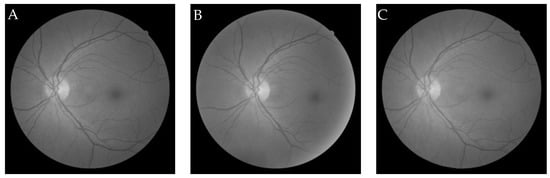

6.2.1. Grey-Wolf Optimization-Based Wang’s Demons Registration